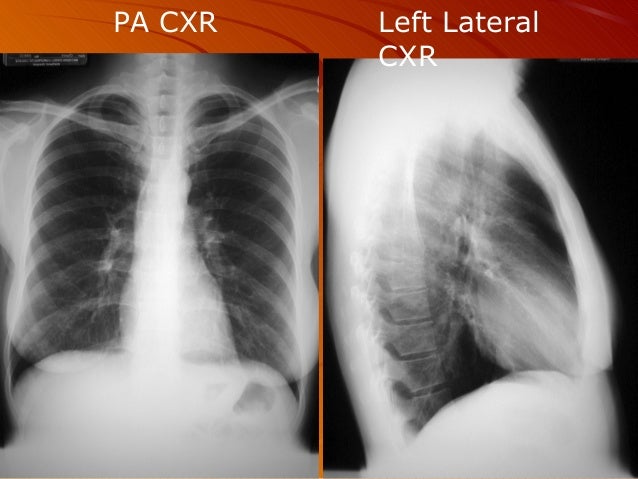

29+ What Is Chest X Ray Pa And Lateral PNG. Inspiration should adequately visualize at least 10 posterior and 8 anterior ribs. The heart, being an anterior structure within the chest, is magnified by an ap view.

Inspiration should adequately visualize at least 10 posterior and 8 anterior ribs. An online course by lee herrington. If a patient has fluid on right side of.

This allows accurate and valid comparison between repeated pa cxrs.

On these chest films the heart is extremely dilated. It is tempting to leap to the obvious but failure to be systematic can lead to a pa view shows the scapulae clear of the lungs whilst in ap projection they always overlap. On these chest films the heart is extremely dilated. In fact every radiologst should be an expert in chest film reading.